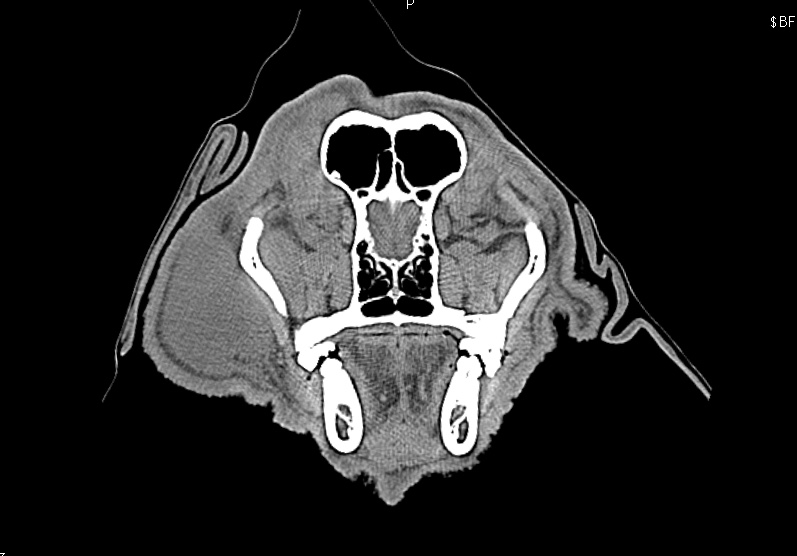

CT検査により外耳から中耳に至る腫瘤の存在が疑われ、耳道軟骨は骨化し、化膿巣は目の下から首にまで達していました。

- 耳道レベルの腫れ、白いのは骨化し崩れた外耳道